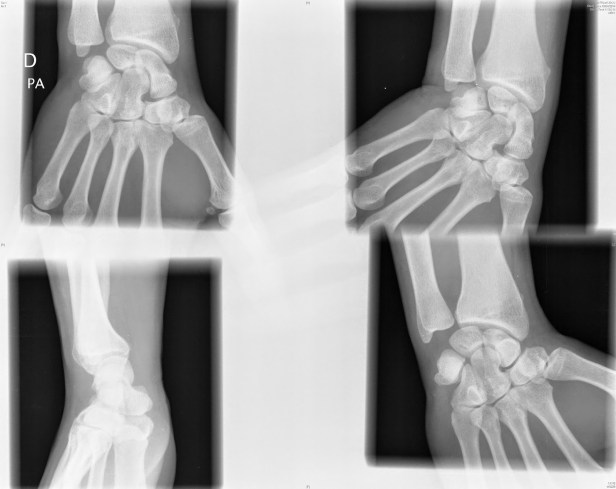

En las siguientes Radiografías vemos lesiones traumáticas de hueso escafoides: la primera es de un paciente de Urgencias, y la segunda es de un paciente con Fractura no consolidada.

Protocolo de rayos x estandarizada con vistas de muñecas extendidas incluyendo la parte distal del radio y las partes proximales de los metacarpianos. Es una serie de cuatro imágenes.

1º.- Vista posterior-anterior estándar con la muñeca en desviación cubital.

2º.- Vista lateral (o de perfil) del carpo y radio / cúbito distal.

3º y 4º.- Vistas oblícuas: una con la mano en el 45 ° de supinación y el otro con 45 ° de pronación.